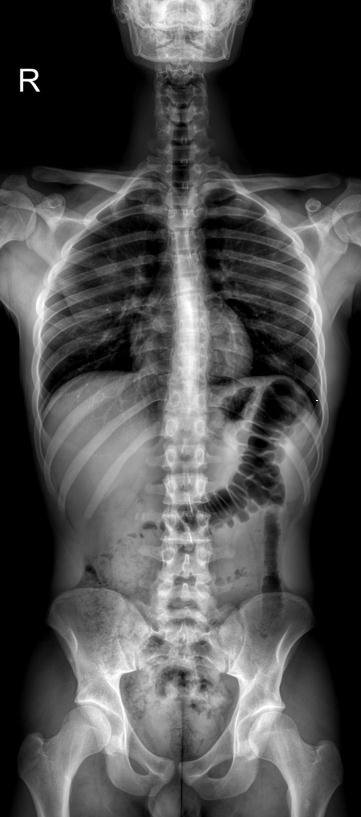

Потребность в рентгене всего позвоночника возникает при его патологическом искривлении ― сколиозе. Это стойкое отклонение позвоночного столба вбок, которое со временем приводит к серьезному искривлению всего скелета и нарушению работы внутренних органов. У взрослых такое заболевание может развиться в результате травм и болезней, но большинство случаев возникает в детском возрасте ― от 6 до 15 лет.

В развитии сколиоза различают 4 степени, которые отличаются величиной искривления, выраженной в градусах угла. Чтобы определить угол, врачу необходимо:

• Сделать рентгенограмму;

• Найти на ней 2 нейтральных, то есть не отклонившихся, позвонка, между которыми есть дуга искривления;

• Провести через них 2 горизонтальные линии перпендикулярно позвоночнику;

• Провести 2 вертикальные линии, перпендикулярные первым;

• Определить угол между второй парой прямых.

В прямом, то есть здоровом позвоночнике линии в парах будут параллельны друг другу, то есть угол составит 0о. При первой степени угол может доходить до 10о, при четвертой ― до 90о. Сколиоз первой степени почти всегда хорошо лечится.

Так как на один четкий снимок попадает не весь позвоночник, а только определенный сегмент, прибегают к стичингу ― склейке или сшивке нескольких снимков в один большой. Делается это виртуально, в цифровом поле, как и измерение углов, что гарантирует высокую точность и минимум погрешности. Переживать за высокий уровень полученной радиации не стоит: в современном оборудовании используется минимально возможное количество излучения. Даже при регулярном обследовании, которое рекомендовано при сколиозе раз в полгода, пациент не набирает допустимую ежегодную дозу.